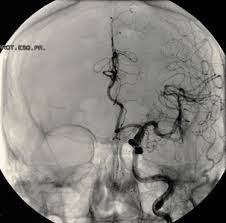

Original Resolution: 1500x1673 Comprehensive Review Of Imaging Of Intracranial Aneurysms And Angiographically Negative Subarachnoid Hemorrhage In Neurosurgical Focus Volume 47 Issue 6 2019 Cerebral angiography confirms the diagnosis of an intracranial aneurysm. 620x322 - An abdominal aortic aneurysm is diagnosed when your abdominal aorta is three centimeters or greater in diameter.

Original Resolution: 473x300 Brain Aneurysms Diagnostic Testing Atlantic Health Aneurysms are usually diagnosed through imaging techniques. 480x360 - By contrast, false aneurysms are external hematomas with a persistent communication to a leaking artery.